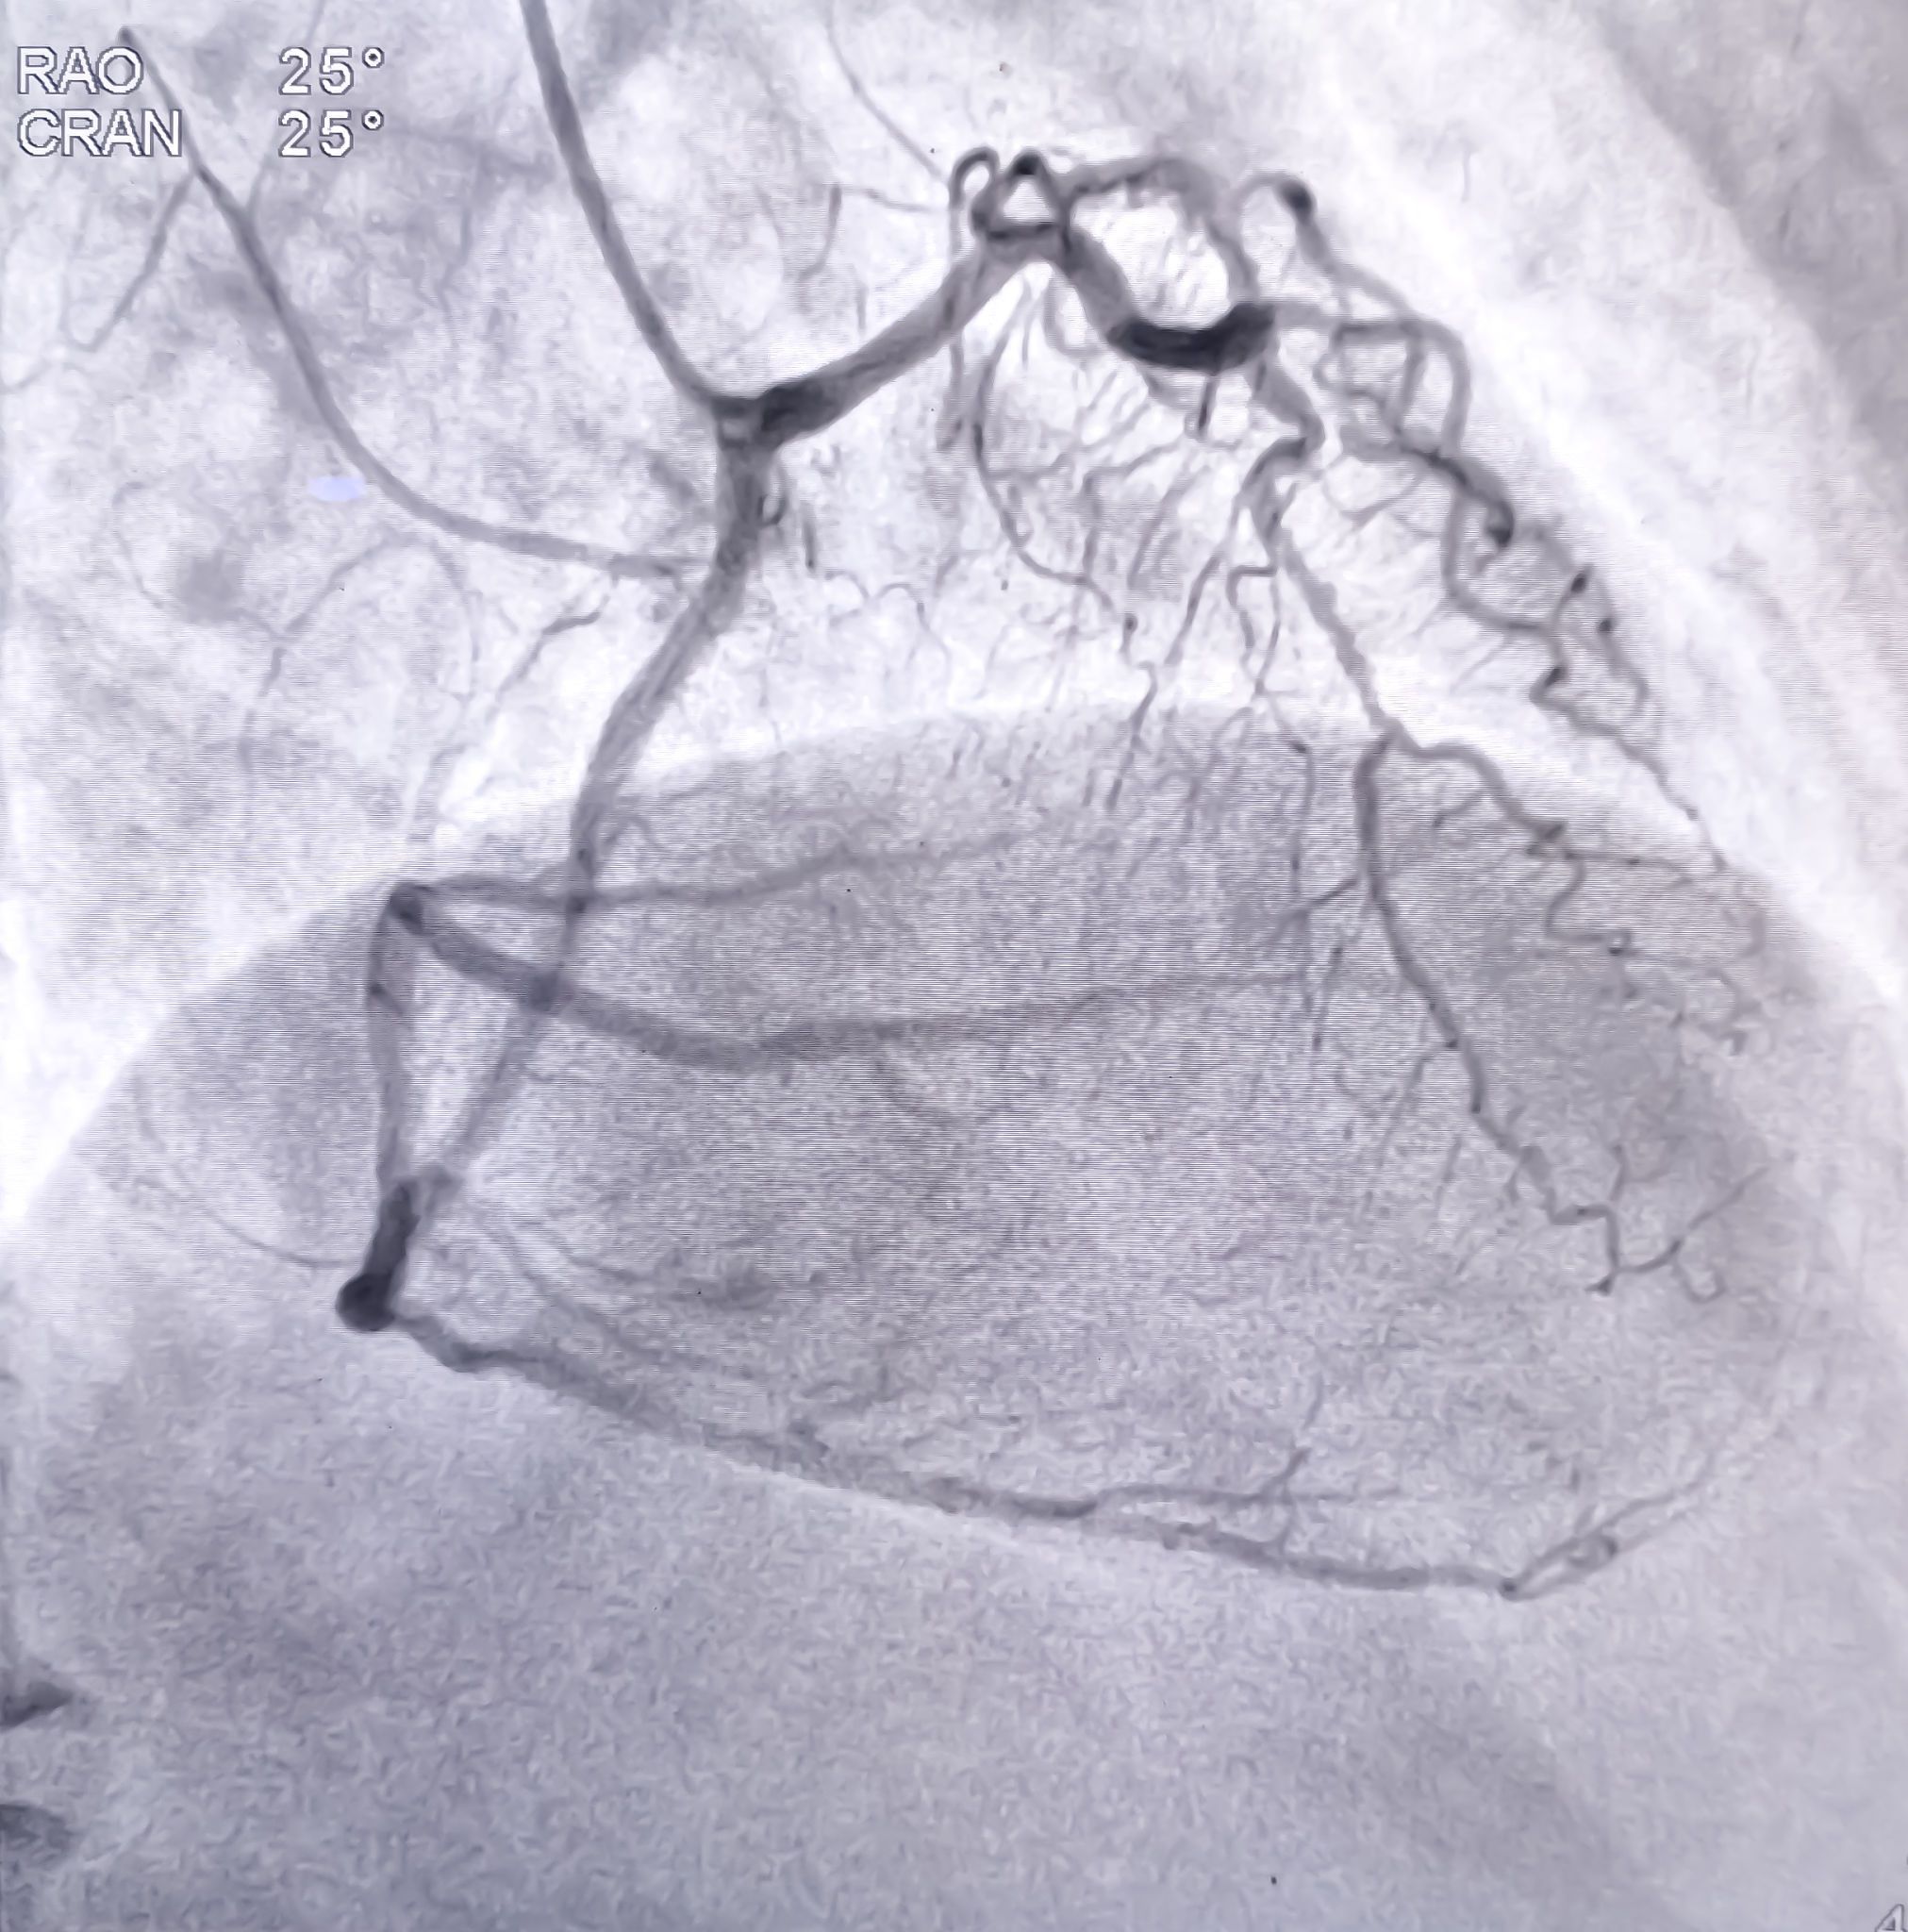

Cardiac Care Excellence

Heart disease remains a leading health concern worldwide, but Germany's cardiac care facilities offer hope through their exceptional services. Patients flock to German hospitals for procedures ranging from heart transplants to minimally invasive valve replacements.

The success rates for cardiac surgeries in Germany are remarkably high, thanks in part to the expertise of the medical teams and the use of advanced techniques. Stories of patients who have overcome life-threatening conditions and now lead healthy lives serve as a testament to the quality of care provided.